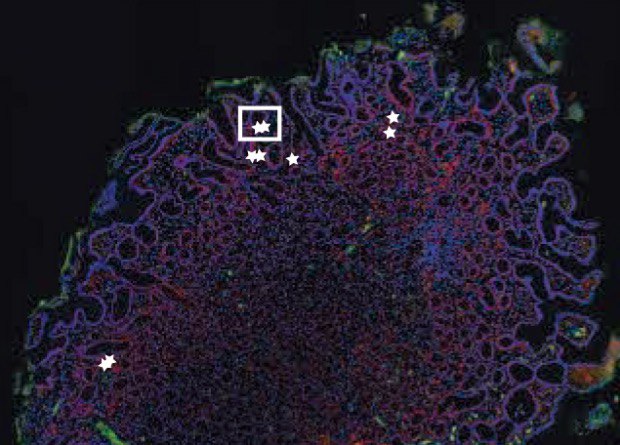

Против коронавируса все средства хороши. Две группы китайских врачей попробовали использовать в борьбе с ним стволовые клетки — и, кажется, преуспели. Правда, как всегда бывает в таких случаях, выборка крайне маленькая, статья еще не отрецензирована, а процедура довольно сложная и дорогая. Едва ли она когда-нибудь станет массовой, но, в любом случае, можно порадоваться за участников этих испытаний — все они быстро пошли на поправку